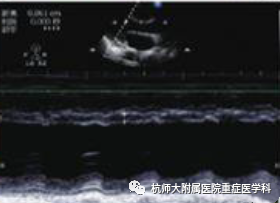

c.胸骨旁长轴切面:主要测量室间隔厚度,左心室射血分数。

什么是超声容积探头重症心脏超声图像的获取_https://www.jmylbn.com_新闻资讯_第33张什么是超声容积探头重症心脏超声图像的获取_https://www.jmylbn.com_新闻资讯_第34张